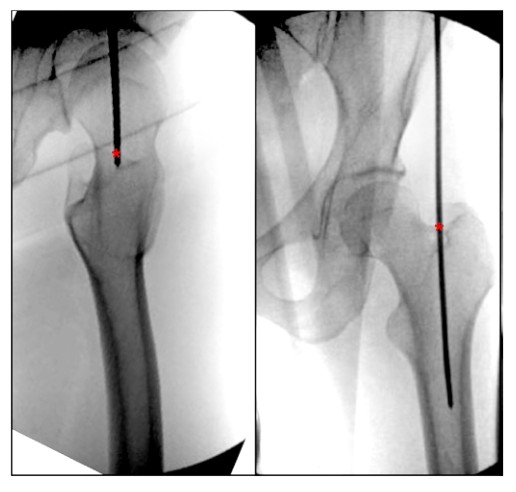

Несколько исследований в современной литературе точно описывают точную точку входа в жемчужную ямку интрамедуллярных бедренных стержней. Georgiadis et al. опишите точку входа в жемчужную ямку как место прикрепления короткого лучевого разгибателя запястья во впадине у основания шейки бедренной кости (рис. 5). Авторы также подчеркнули, что точка входа, расположенная слишком далеко вперед или слишком далеко внутрь, может увеличить риск перелома шейки бедра, а когда точка входа расположена слишком далеко назад, может возникнуть высокий риск ишемического некроза, который выше у пациентов подросткового возраста.

Рисунок 5. Фронтолатеральный вид бедра во время операции, показывающий идеальную точку входа для ретроградного интрамедуллярного стержня грушевидной ямки. Символ «*» указывает на начальную точку интрамедуллярного стержня.